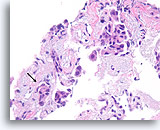

Ductaal carcinoom in situ, Borst FNA, Celblok.

Vergeleken met de onregelmatige, infiltratieve groepen zijn in deze afbeelding de vier profielen van maligne ductale cellen alle omgeven door een glad, dicht, helderroze collageen basaalmembraan. Merk op hoe de fibroblasten net buiten het basaalmembraan zijn georganiseerd met hun lange as parallel aan het basaalmembraan (pijlen). Net als bij kernbiopten van de borst sluit de afwezigheid van invasiviteit in dit ene plaatje geen invasiviteit uit in andere gebieden.

40X

Ductaal carcinoom in situ, Borst FNA, Celblok.

Vergeleken met de onregelmatige, infiltratieve groepen zijn in deze afbeelding de vier profielen van maligne ductale cellen alle omgeven door een glad, dicht, helderroze collageen basaalmembraan. Merk op hoe de fibroblasten net buiten het basaalmembraan zijn georganiseerd met hun lange as parallel aan het basaalmembraan (pijlen). Net als bij kernbiopten van de borst sluit de afwezigheid van invasiviteit in dit ene plaatje geen invasiviteit uit in andere gebieden.

40X

Ductaal carcinoom, Borst FNA, Celblok.

Dit plaatje toont geen normale lobulaire architectuur en de stromale fibroblasten zijn niet goed uitgelijnd met de ductale cellen (pijl). Invasiviteit kan echter niet met zekerheid worden gediagnosticeerd omdat de maligne ductale cellen in dit gebied ronde aggregaten vormen met een gladde, dichte, collagene laag die hen van het stroma scheiden. Soortgelijke patronen kunnen worden waargenomen als een ductaal carcinoom in situ zich uitbreidt tot sceloserende adenose. Een afwezigheid van myoepitheliale cellen volgens IHC kan helpen aantonen dat deze focus invasief is [12].

40x

Ductaal carcinoom, Borst FNA, Celblok.

Dit plaatje toont geen normale lobulaire architectuur en de stromale fibroblasten zijn niet goed uitgelijnd met de ductale cellen (pijl). Invasiviteit kan echter niet met zekerheid worden gediagnosticeerd omdat de maligne ductale cellen in dit gebied ronde aggregaten vormen met een gladde, dichte, collagene laag die hen van het stroma scheiden. Soortgelijke patronen kunnen worden waargenomen als een ductaal carcinoom in situ zich uitbreidt tot sceloserende adenose. Een afwezigheid van myoepitheliale cellen volgens IHC kan helpen aantonen dat deze focus invasief is [12].

40x